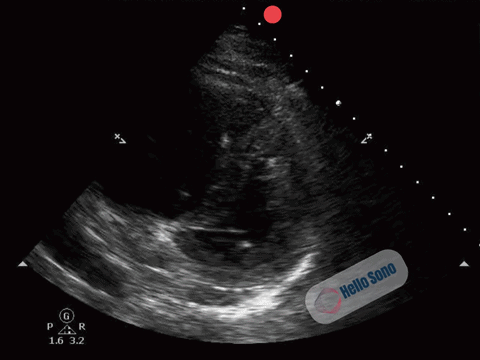

With persistent concern for pulmonary embolism (PE), the clinician proceeds with a focused cardiac POCUS exam. A representative parasternal short-axis (PSSA) view at the level of the papillary muscles is shown below.

Clip 1: Parasternal short-axis view at the level of the papillary muscles.

Clip 1: Parasternal short-axis view demonstrating right ventricular enlargement (right side of the screen) and septal flattening, resulting in a D-shaped left ventricle consistent with right ventricular pressure overload.

The PSSA view demonstrates a flattened interventricular septum, creating a D-shaped left ventricle instead of the normal circular contour.

In addition, the right ventricle (RV) appears enlarged relative to the left ventricle on this view. The RV cavity occupies a larger proportion of the image than expected.

The combination of RV enlargement and septal flattening reflects acute right ventricular pressure overload.

In the appropriate clinical context, these findings are highly concerning for acute PE.